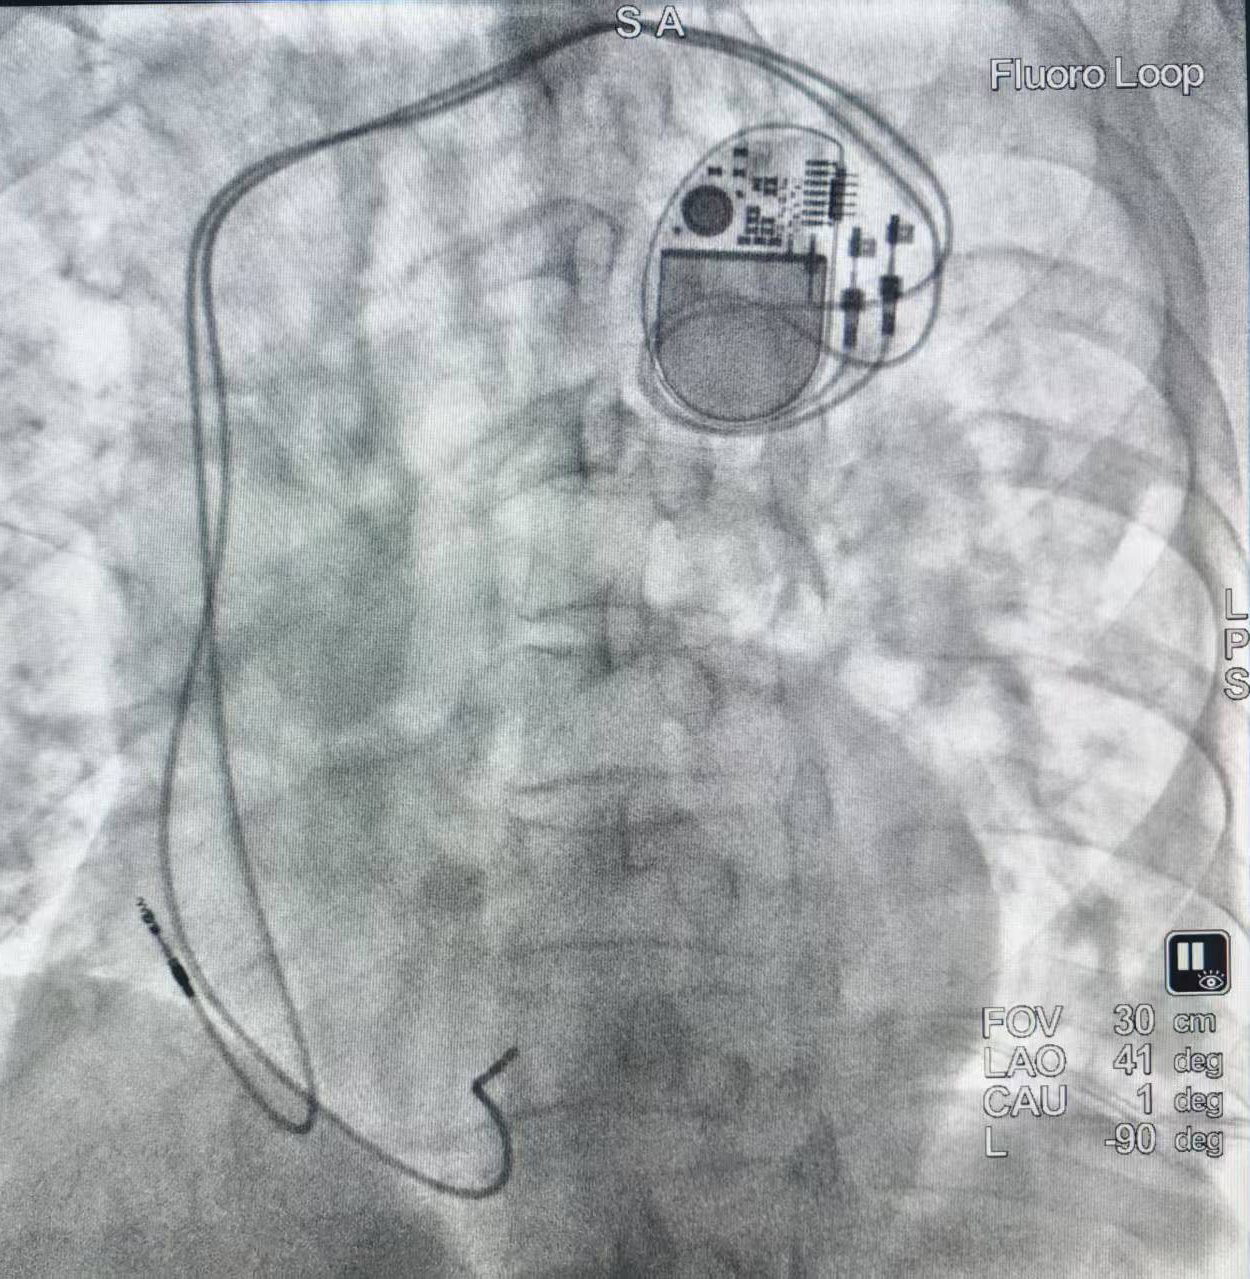

11月12日上午,在中南大学湘雅二医院桂林医院叠彩院区,一场与时间赛跑的生命守护战顺利告捷。面对“高度房室传导阻滞”和多种基础疾病带来的极高手术风险,心血管内科执行副主任陈明鲜团队迎难而上,成功为患者植入双腔心脏起搏器,为这颗鲐背老人的心脏注入了新的活力。

面对这一高难度病例,陈明鲜副主任带领团队沉着应对,对患者进行了全面评估,并据此制定了详尽且个性化的手术方案与应急预案。手术台上,团队凭借精湛的穿刺技术和清晰的影像引导,将心室与心房导线精准定位,起搏功能即刻反应良好。整台手术精准高效,术中出血量少,患者生命体征始终平稳。